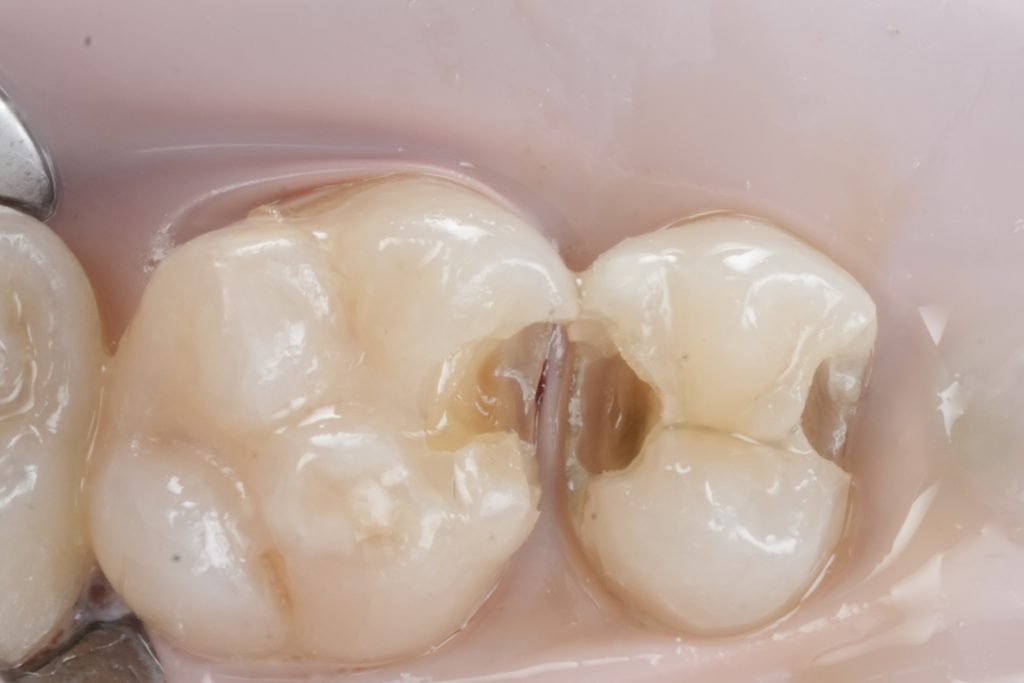

Images to place

- Fig. 5: Prepared cavity occlusal view.

- Fig. 6: Proximal box close-up (after caries removal).